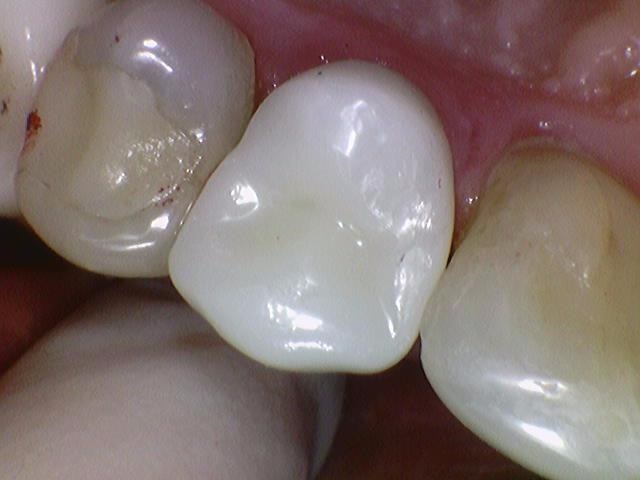

생체친화적이면서, 치아색이 나고, 단단한

지르코니아를 크라운 재료로 대부분의 치과에서 쓴지 꽤 되었습니다.

많이 썩은 치아 신경치료 후 지르코니아 크라운 [시청역 연세예감치과]

많이 썩은 치아 신경치료 후 지르코니아크라운[시청역 연세예감치과]